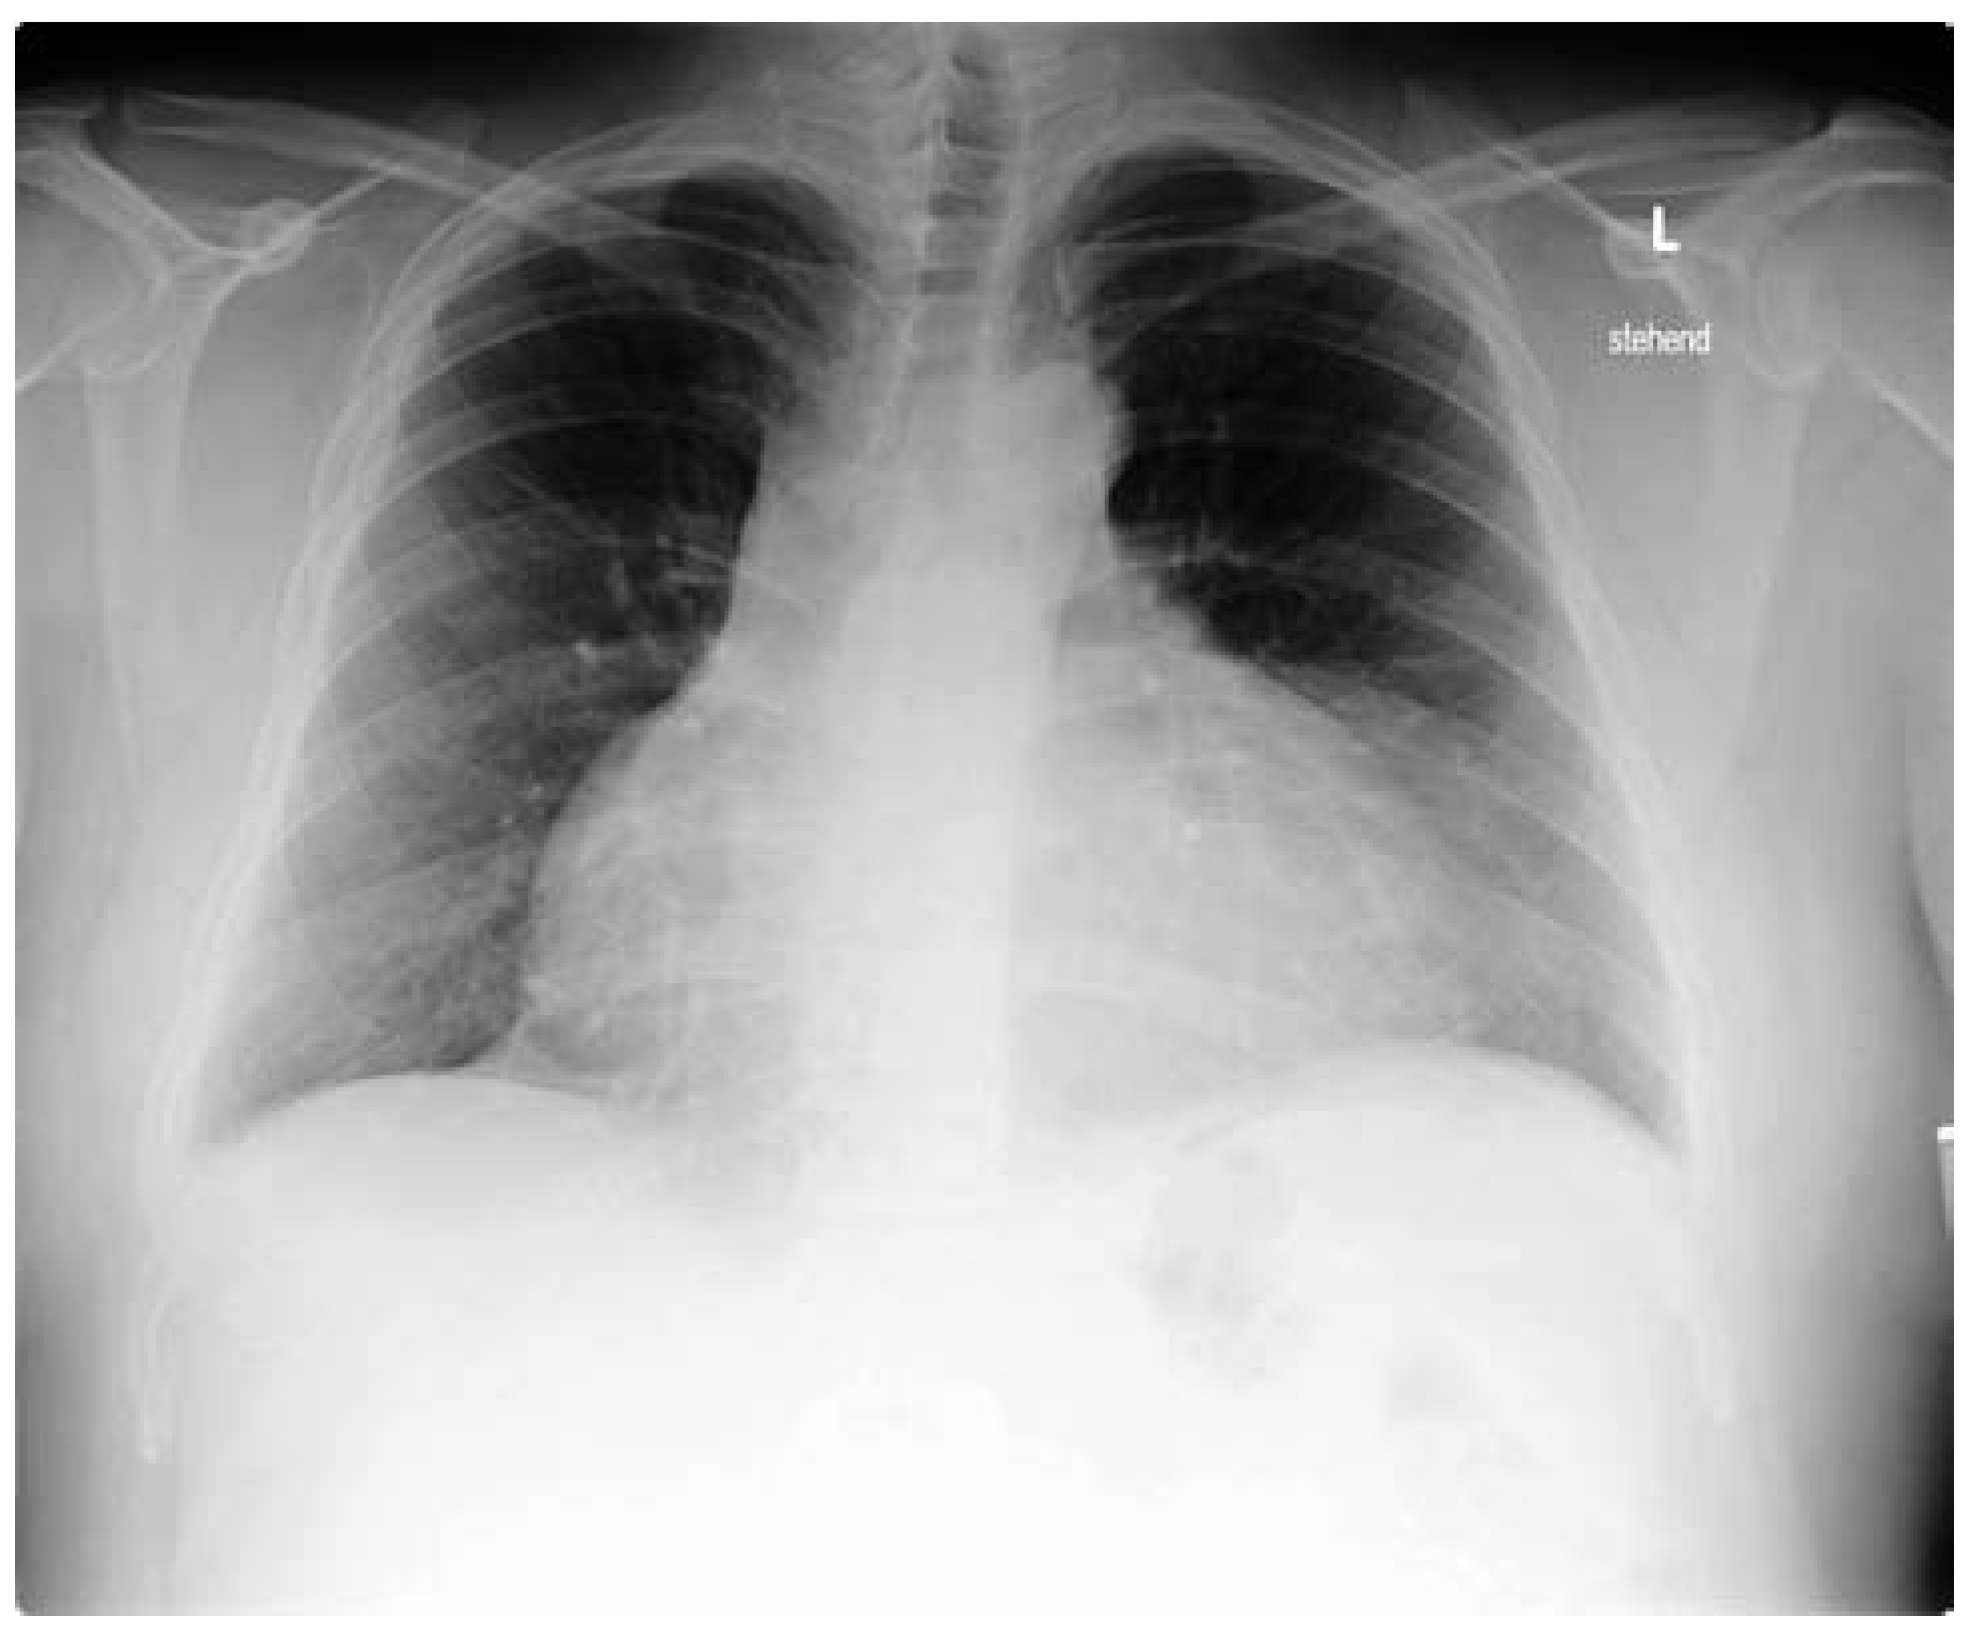

Abbildung 1. Thoraxröntgen bei Eintritt mit ausgeprägter Kardiomegalie und kugeliger Herzkonfiguration sowie zeltförmiger Ausziehung ins obere Mediastinum.

Ein 31-jähriger, türkischstämmiger Patient stellte sich mit retrosternalem Druck und progredienter Dyspnoe auf unserer Notfallstation vor; aus der Vorgeschichte war ein unklarer, chronischer Perikarderguss bekannt, welcher bisher als nicht punktionswürdig betrachtet wurde. Im Status präsentierte sich ein tachykarder, normotensiver Patient, ein Pulsus paradoxus lag nicht vor. Die laborchemischen Untersuchungen waren bis auf eine leichte CRP-Erhöhung bland. Im Thoraxröntgen (Abb. 1) fand sich eine ausgeprägte Kardiomegalie mit kugelig konfigurierter Herzschattengrösse, elektrokardiographisch (Abb. 2) ein alternierender QRS-Ausschlag. Die Echokardiographie bestätigte einen eindrücklichen Perikarderguss (zirkulärer perikardialer Erguss von 2,5–3 cm, Abb. 3) mit Zeichen der Prätamponade. In der anschliessend durchgeführten Perikardiozentese konnten 1000 ml hämorrhagischer Erguss drainiert werden, worauf sich Symptomatik und Tachykardie des Patienten unmittelbar verbesserten. Die zytologische und bakteriologische Untersuchung blieb ohne Resultat, ein Quantiferon-Test war negativ. Anamnestisch und klinisch bestanden keine Hinweise für ein familiäres Mittelmeerfieber.